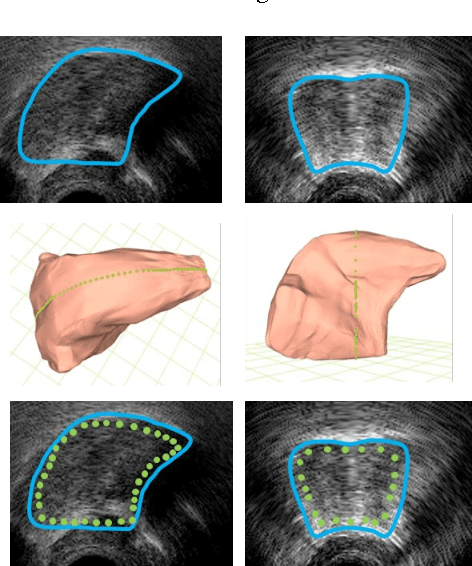

Abstract:This article describes a contour-based 3D tongue deformation visualization framework using B-mode ultrasound image sequences. A robust, automatic tracking algorithm characterizes tongue motion via a contour, which is then used to drive a generic 3D Finite Element Model (FEM). A novel contour-based 3D dynamic modeling method is presented. Modal reduction and modal warping techniques are applied to model the deformation of the tongue physically and efficiently. This work can be helpful in a variety of fields, such as speech production, silent speech recognition, articulation training, speech disorder study, etc.